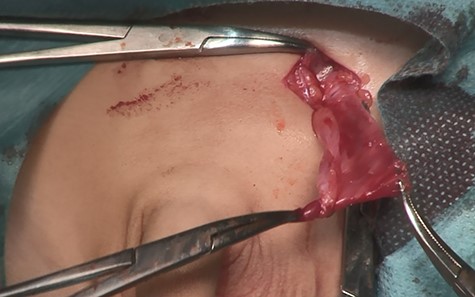

A14-month-old boy was admitted to our hospital to undergo inguinal orchidopexy. At the age of 1 month, the left testis was palpable between the inguinal canal and the scrotum. When he was 6 months old, ultrasonography showed the left testis inside the inguinal canal (Fig. 1). At the age of 13 months, the patient was seen in the outpatient clinic for preoperative examination in preparation for inguinal orchidopexy; the left testis was not palpable at that time. At the age of 14 months, we began surgery with a preoperative diagnosis of an undescended testis. When the inguinal canal was opened, only a patent processus vaginalis was visible (Fig. 2). After incision of the membrane, we were able to retrieve the testis from the abdominal cavity (Fig. 3a). The patent processus vaginalis was closed, a dartos pouch was created and the testis was guided into the pouch and fixed to its wall (Fig. 3b).

Intraoperative photography (14 months of age). (a) The testis is retrieved from the abdominal cavity. (b) After the patent processus vaginalis is closed, the testis is guided into a dartos pouch and fixed to the pouch wall.